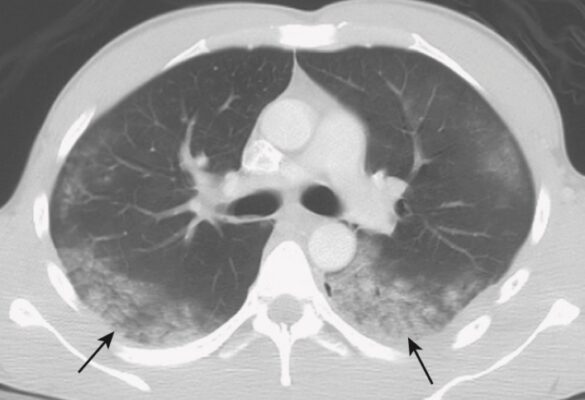

Viêm phổi do hít (Aspiration)

- Có nhiều nguyên nhân dẫn đến tình trạng hít dị vật vào cây khí phế quản, trong số đó có các bệnh lý thần kinh (đột quỵ, chấn thương sọ não), thay đổi trạng thái tâm thần (gây mê, dùng thuốc phiện quá liều), trào ngược dạ dày thực quản và hậu phẫu vùng đầu cổ.

- Hít phải hầu như luôn xảy ra ở những phần thấp nhất của phổi.

- Khi một người ở tư thế dựng thẳng, các phần thấp nhất của phổi thường là các thùy dưới. Bên phải thường bị nhiều hơn bên trái vì phế quản chính bên phải thẳng hơn và rộng hơn.

- Hít phải cấp tính sẽ tạo các dấu hiệu X quang của bệnh khoảng chứa khí.

- Vị trí, tốc độ xuất hiện và nhóm bệnh nhân có khuynh hướng hít phải là những manh mối cho nguyên nhân của hít phải (Hình 8).